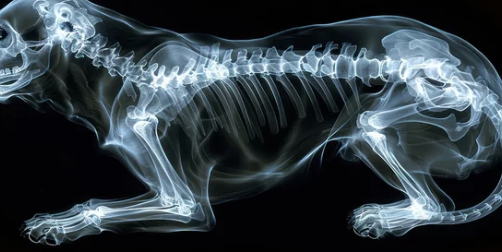

슬개골 탈구는 강아지의 무릎뼈가 제자리를 벗어나는 질환이에요.